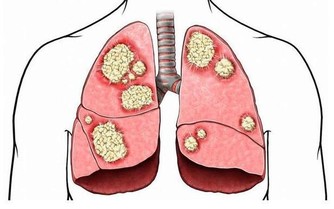

肩背有拉扯般的疼痛感,以為是肩周炎,等著自愈,半年過去了,疼痛不斷加劇,

進一步檢查後才發現原來是胰腺壞了。

前兩天,姚女士拿到診斷報告時覺得不可思議,

她說,自己除了肩背疼和腸胃差外,沒有其它不適反應。

半年前,姚女士開始覺得肩膀隱隱作痛,因為年逾50歲,她判斷自己患上了「五十肩」。

之後,姚女士頻繁求醫,換了兩家醫院,做了多項檢查,

終於找到害她肩背疼痛的「元兇」——胰腺癌。

醫生說,這些症狀已經在提示姚女士胰腺壞了。

胰腺疾病不容易發現,如果能早點注意到發病信號,對治療很有幫助。

他介紹,現代人的飲食結構中,肉、蛋、奶和精細食物增多,蔬菜、粗糧減少,

再加上抽菸、喝酒、吃燒烤等不良習慣,導致胰腺疾病的發病率增多,且逐漸年輕化。

以前,胰腺癌患者基本都是五六十歲以上的人,而現在,30多歲的患者也時而可見。